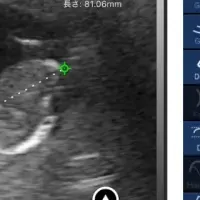

画像1